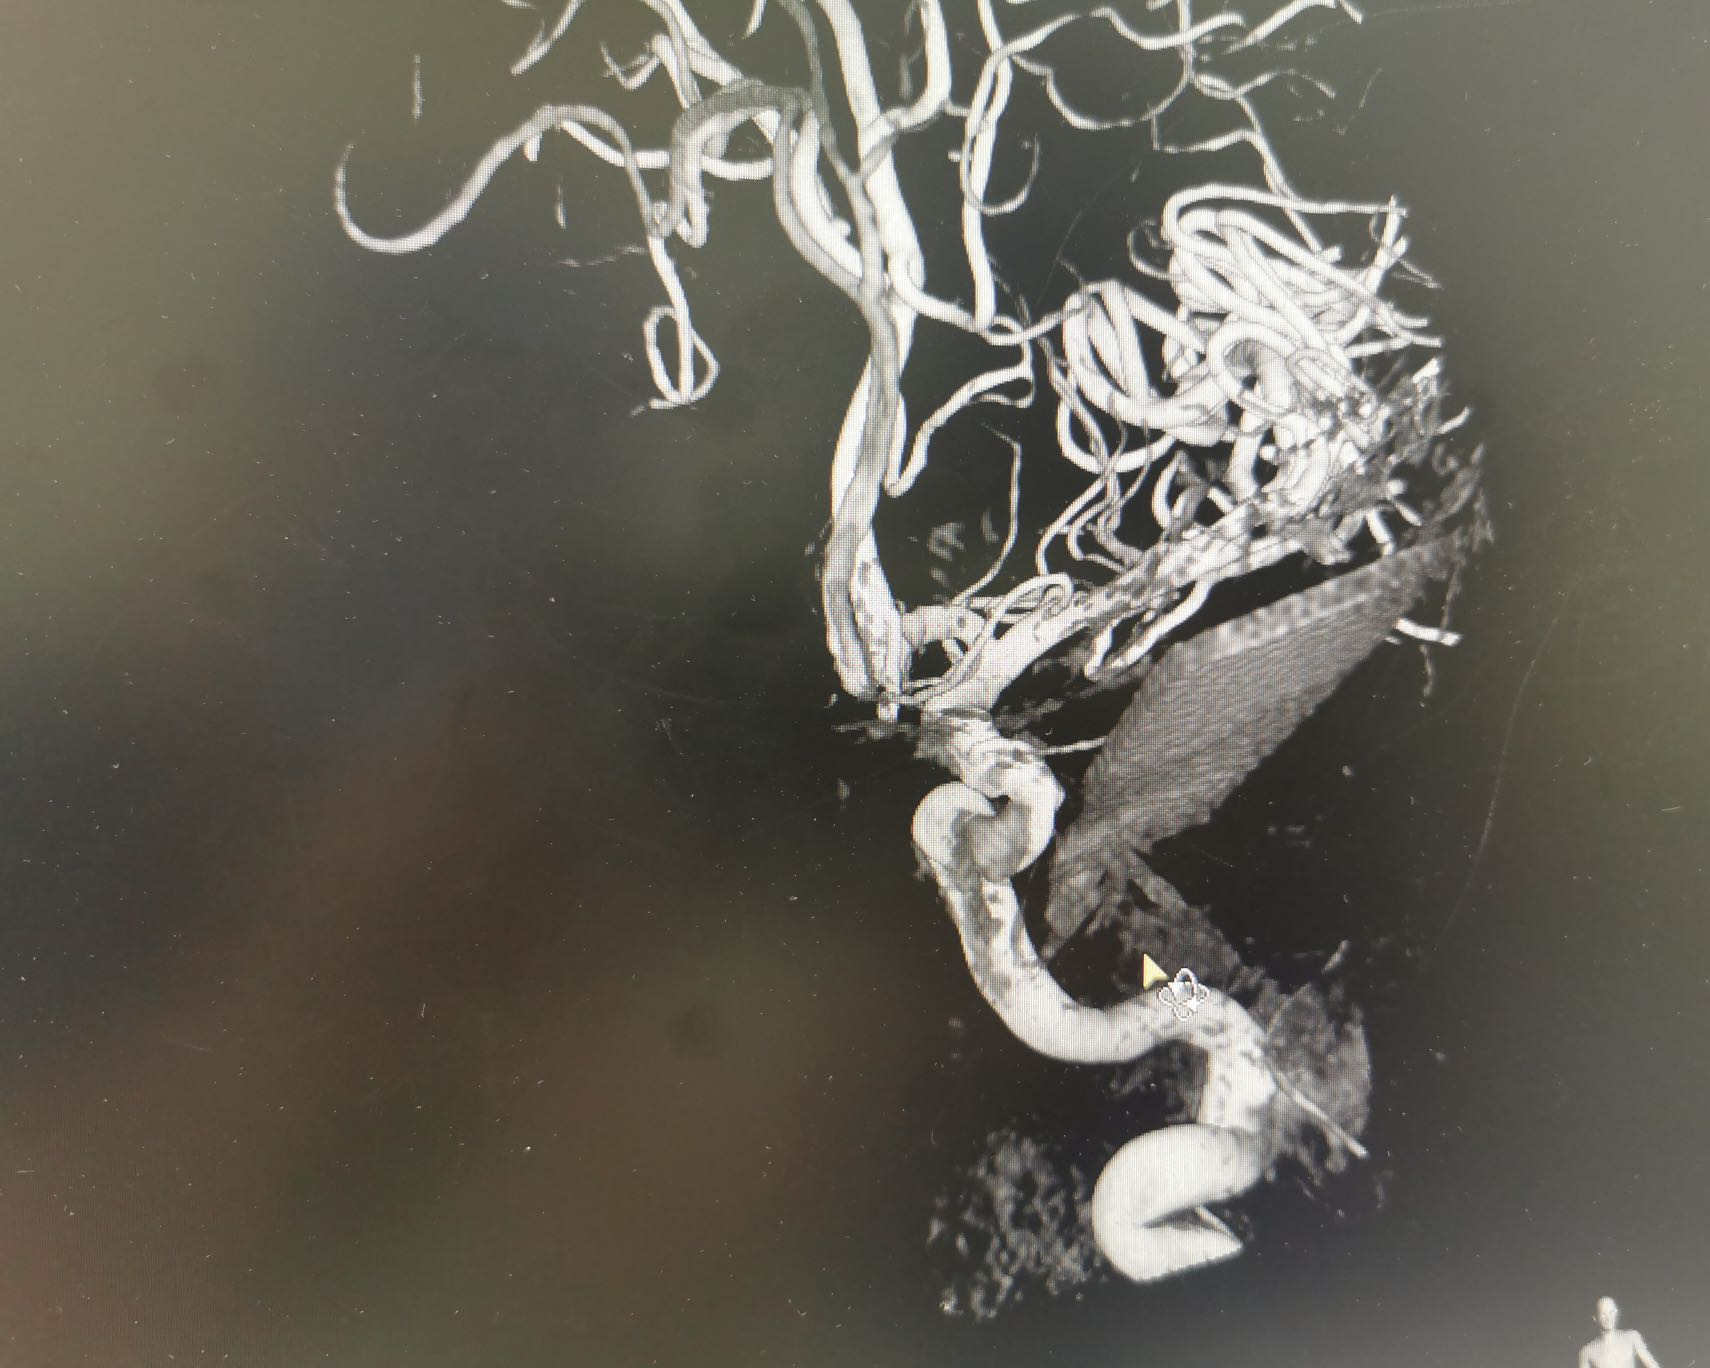

在充分术前准备和各科室的紧密配合下,一场“虎口拔牙”式的开颅探查+异物取出手术在中心手术室1号杂交手术间紧张有序地开始了。神经外科康军主任坐镇指挥,手术室王蕊、李家兴护士迅速完成各项准备,麻醉科吴黎黎医生为病人进行全身麻醉。神经外科王卫医生首先为患者进行全脑血管造影术(DSA),造影结果显示异物与颅内海绵窦段颈内动脉“擦身而过”,最近处仅有不足2毫米的间隙!玻璃断茬异常锐利,在拔出过程中稍有不慎,就很有可能伤及颅内大血管,引起致命大出血。王卫医生又给患者做了压颈试验,证实前交通动脉代偿良好。如果现在闭塞左侧颈内动脉,手术风险和医生压力将会大大降低,但患者会面临迟发偏瘫或将来脑供血不足等风险,神经外科医生们又面临一个两难选择。经过现场认真讨论,为保证患者术后能拥有高质量的健康生活,康军主任果断决定:力争为患者保留颈内动脉畅通,同时留置腹股沟处介入血管穿刺鞘,万一术中出现大出血情况可以迅速闭塞患侧颈内动脉近端。

患者造影结果